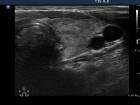

Follow-up examinations (rows from 1st to 8th):

2. Note the relation between volume, echogenicity, vascularization and hormone levels.